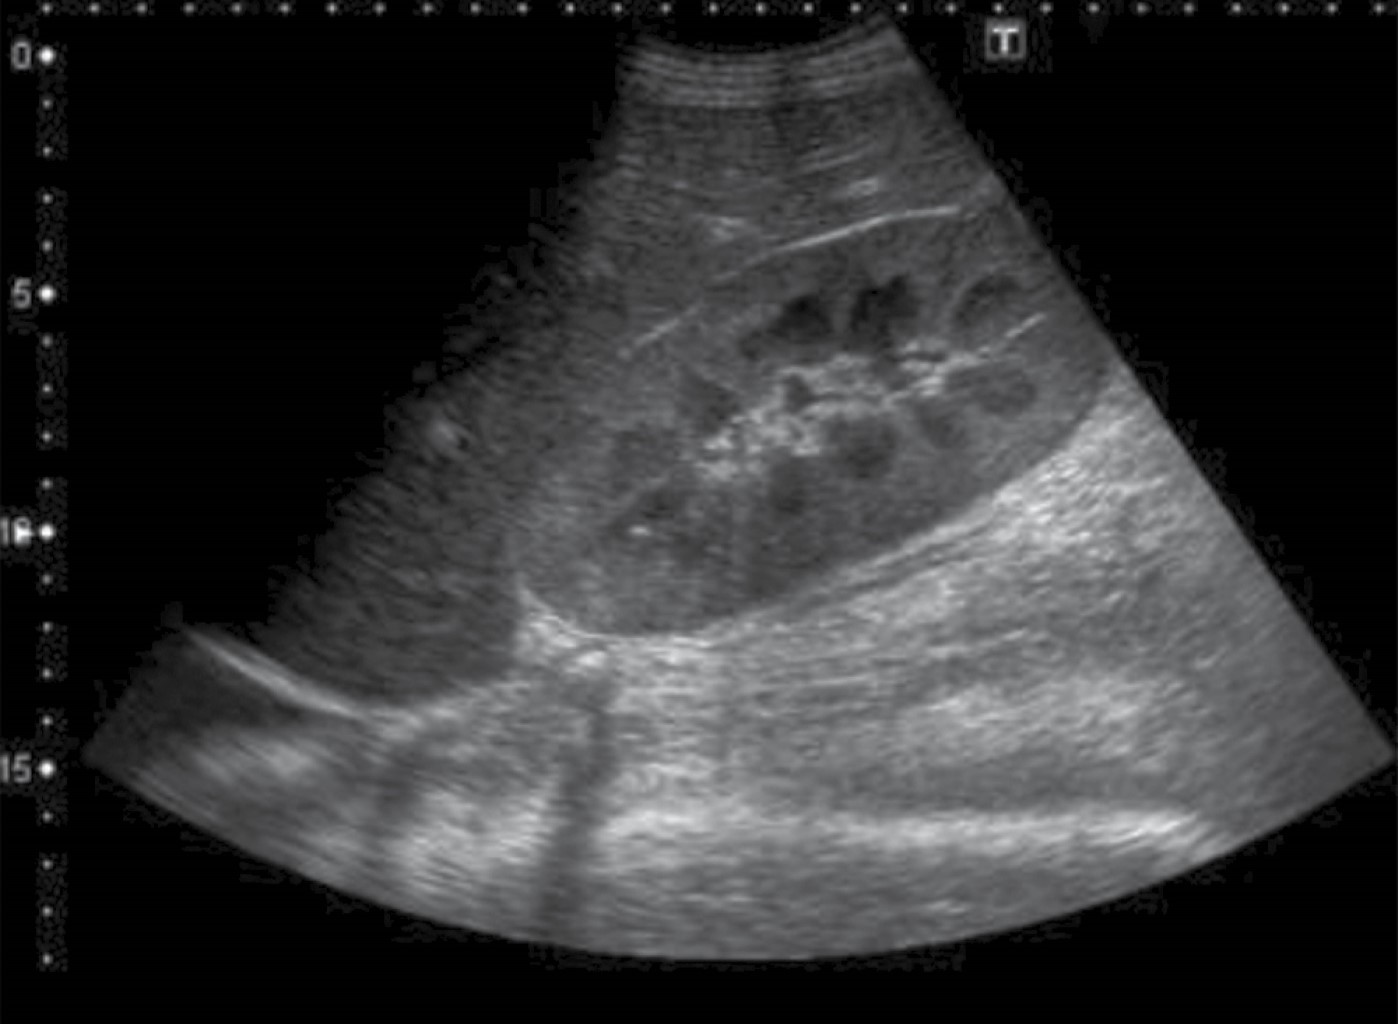

La toma de muestras de arterias renales interlobares o arcuatas con ecografía Doppler pulsado permite obtener un perfil de "baja resistencia" propio de los territorios con alta perfusión en reposo. En las arterias intrarrenales, la morfología clásica de la forma de onda Doppler se caracteriza por pico sistólico pronunciado, seguido de un movimiento ascendente, con el llamado pico sistólico temprano; por una parte, decreciente de la onda que representa su componente diastólico, combinando los elementos principales del análisis espectral, el índice de resistencia renal se puede calcular a través de la siguiente fórmula:

IRR = (velocidad sistólica máxima-velocidad diastólica final) / velocidad sistólica máxima11

Se realizó un estudio descriptivo, longitudinal, prospectivo y unicéntrico. Se incluyeron 42 pacientes de la unidad de terapia intensiva del Hospital Angeles Pedregal, en el periodo comprendido de febrero a mayo de 2022, con diagnóstico de sepsis y choque séptico de cualquier foco, se realizó Doppler renal a su ingreso y medición posterior a uso de vasopresor (Figuras 1 y 2). Se obtuvieron valores mediante Doppler renal de índices de resistencia renal basal en pacientes con diagnóstico de sepsis a su ingreso a la unidad de terapia intensiva, evolucionando a choque séptico e inicio de vasopresor, se realizaron mediciones para obtener nuevamente el índice de resistencia renal y registrar sus cambios en casos dependientes de vasopresor para mantener PAM arriba de 65 mmHg. Las anotaciones y cambios de éstos se realizaron por el investigador y un segundo observador para corroborar la adecuada posición de transductor, así como localizar la arteria interlobar (Figuras 3 y 4).